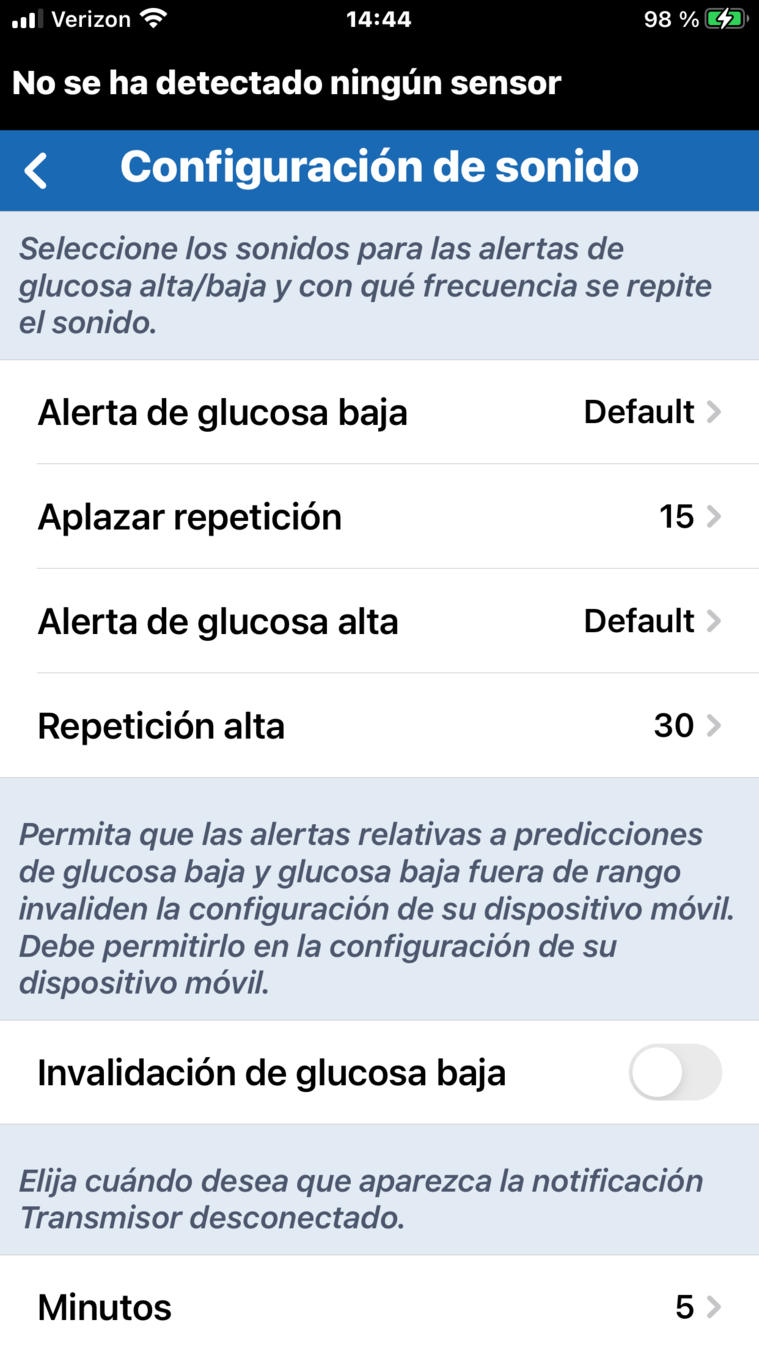

Otra forma importante en la que puede personalizar su sistema de MCG Eversense® E3

es adaptando el sonido de las alertas

y la frecuencia con la que se repiten.

CONFIGURACIÓN DE SONIDO PERSONALIZADA

En la pantalla de inicio Mi glucosa, toque el icono del menú principal.

CONFIGURACIÓN DE SONIDO PERSONALIZADA

A continuación, toque Configuración

en el menú principal.

En la pantalla de inicio Mi glucosa, toque el icono del menú principal.

Después elija Configuración de sonido.

CONFIGURACIÓN DE SONIDO PERSONALIZADA

A continuación, toque Configuración

en el menú principal.

En la pantalla de inicio Mi glucosa, toque el icono del menú principal.

En la pantalla Configuración de sonido,

puede tocar el nombre de una alerta para abrir un menú de tonos que le permite establecer

un sonido especial para esa alerta concreta.

CONFIGURACIÓN DE SONIDO PERSONALIZADA

Por ejemplo, para cambiar el sonido de alerta de glucosa baja, toque el nombre del tono para escuchar cómo suena y decidirse.

CONFIGURACIÓN DE SONIDO PERSONALIZADA

En la pantalla Configuración de sonido, puede tocar el nombre de una alerta para abrir un menú de tonos que le permite establecer un sonido especial para esa alerta concreta.

CONFIGURACIÓN DE SONIDO PERSONALIZADA

Puede cambiar su elección tocando el nombre de otro tono.

Por ejemplo, para cambiar el sonido de alerta de glucosa baja, toque el nombre del tono para escuchar cómo suena y decidirse.

En la pantalla Configuración de sonido, puede tocar el nombre de una alerta para abrir un menú de tonos que le permite establecer un sonido especial para esa alerta concreta.

FUNCIÓN DE REPETICIÓN DE ALERTAS

La función de repetición de alertas

le permite definir la frecuencia con

la que le gustaría que se repita una alerta.

Basta con tocar la opción de repetición.

FUNCIÓN DE REPETICIÓN DE ALERTAS

Desplácese para definir el tiempo. A continuación, toque OK.

La función de repetición de alertas

le permite definir la frecuencia con

la que le gustaría que se repita una alerta.

Basta con tocar la opción de repetición.

FUNCIÓN DE REPETICIÓN DE ALERTAS

En este ejemplo, en el que el ajuste de repetición de alerta de glucosa baja está definido en 15 minutos, el usuario recibirá una alerta de glucosa baja cada 15 minutos siempre que el nivel de glucosa permanezca por debajo del umbral de alerta de glucosa baja.

La función de repetición es una característica importante que debe entender si considera que debe

ajustarse la frecuencia con la que

recibe las alertas.

FUNCIÓN DE REPETICIÓN DE ALERTAS

En este ejemplo, en el que el ajuste de repetición de alerta de glucosa baja está definido en 15 minutos, el usuario recibirá una alerta de glucosa baja cada 15 minutos siempre que el nivel de glucosa permanezca por debajo del umbral de alerta de glucosa baja.